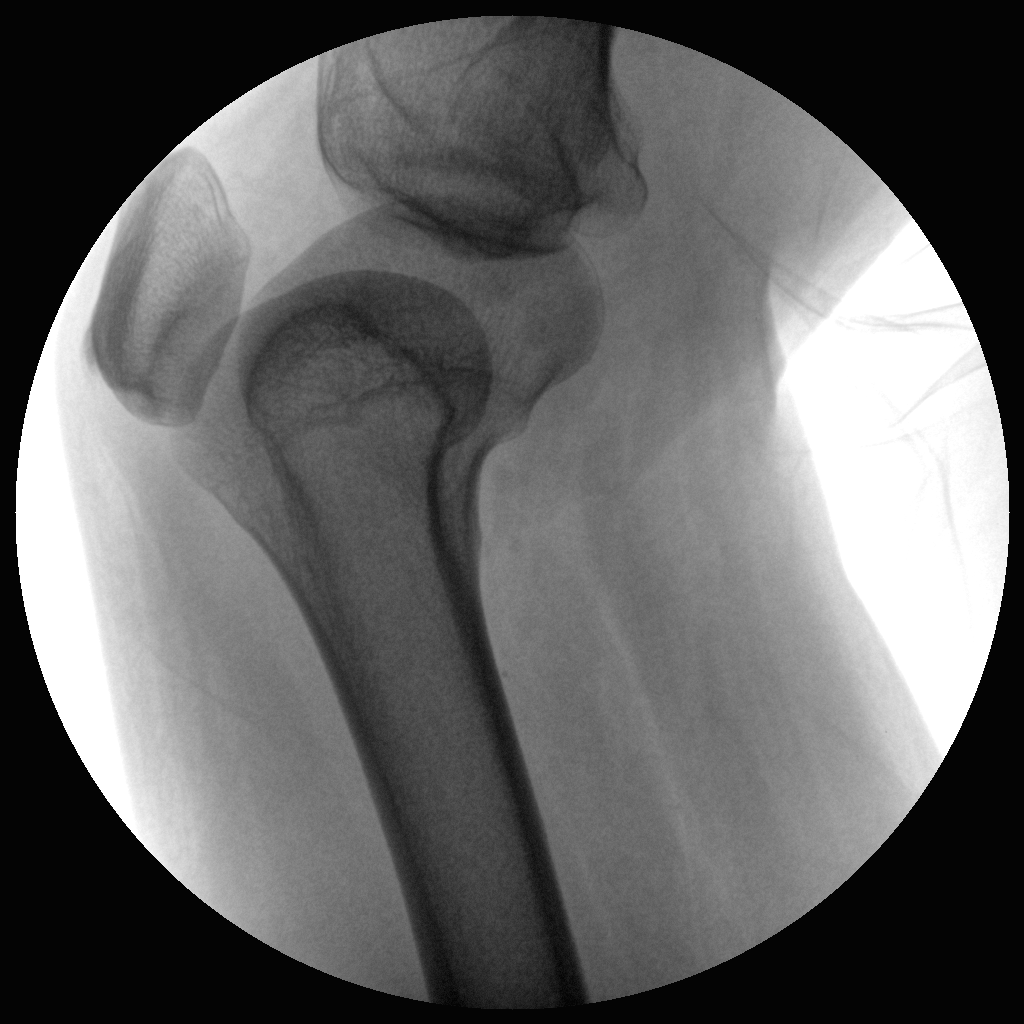

Clinical picture

临床图片